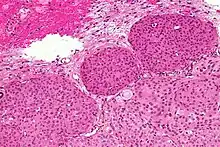

- A woven architectural pattern

- Psammoma bodies (spheroid calcifications)

- Syncytial cells (having indistinct cell membranes) with eosinophilic (pink) cytoplasms

- Round uniform nuclei

- Whorls (concentric cell arrangements)[15]

Histologically, meningioma cells are relatively uniform, with a tendency to encircle one another, forming whorls and psammoma bodies (laminated calcific concretions).[18] As such, they also have a tendency to calcify and are highly vascularized.